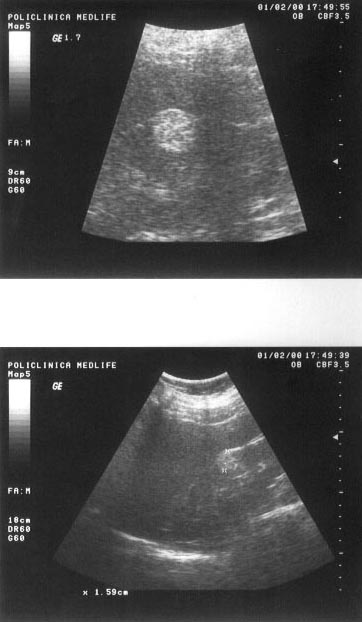

Figura 5. Hemangiom hepatic lobul stang

Figura 6. Hemangiom renal - la nivelul treimii medii a

rinichiului drept, mica zona hiperecogena, rotunda, care deformeaza conturul

renal.